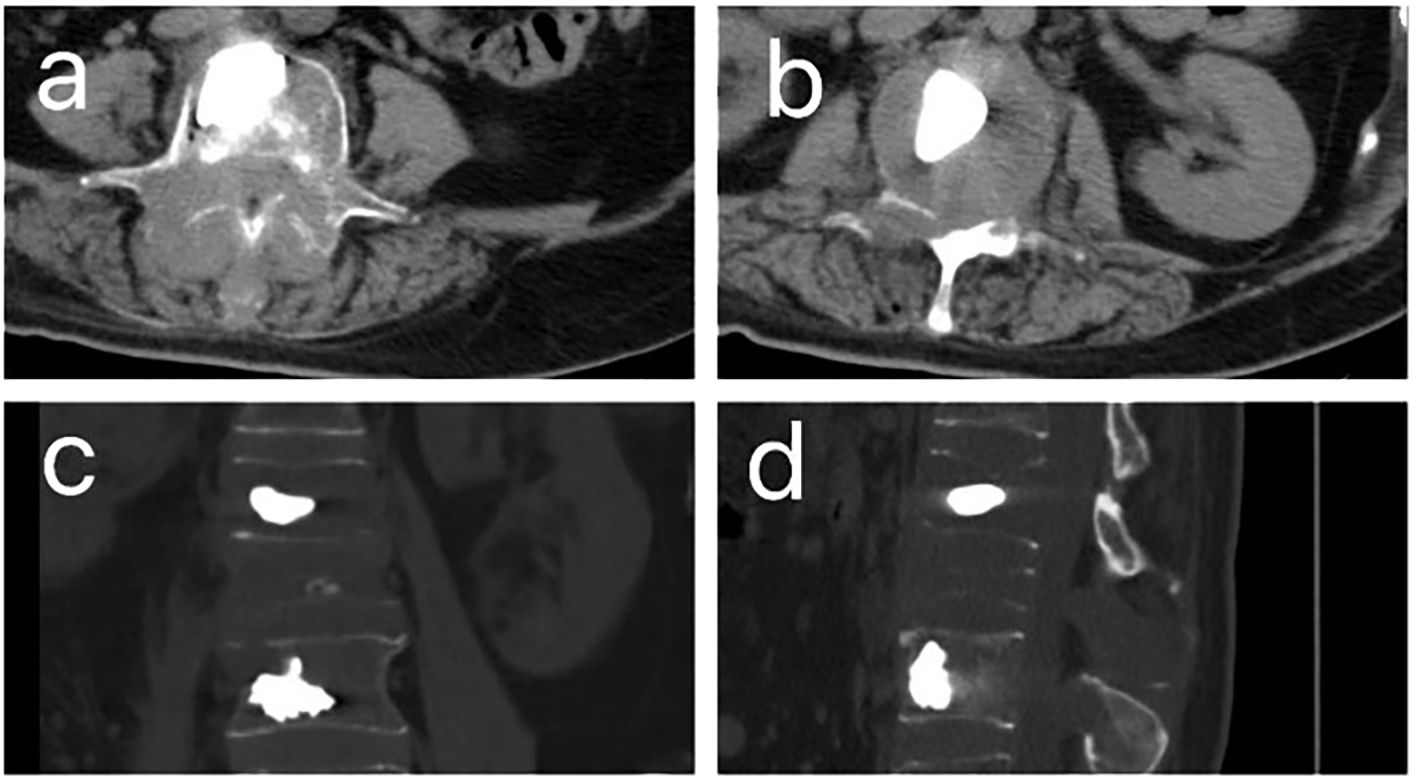

A 48-year-old woman presented with a 2×3 cm right breast mass discovered during routine physical examination. Following simple lumpectomy at a local hospital, pathological examination confirmed primary breast leiomyosarcoma (Figure 1), which was subsequently verified by our institutional review. The patient received no adjuvant therapy postoperatively. Two years later, she developed progressive lower back pain refractory to non-steroidal anti-inflammatory drugs (NSAIDs), accompanied by lumbar stiffness and ambulatory difficulty. Initial lumbar magnetic resonance imaging (MRI) demonstrated compression fractures without definitive intervention, and her symptoms progressively worsened to complete mobility impairment.

Figure 1. CT images after percutaneous kyphoplasty (PKP) of patient. (A, B). The horizontal plane CT image of patient after PKP. (C). The coronal CT images of patient after PKP. (D) The sagittal CT images of patient after PKP.

Ten months following symptom onset, repeat MRI revealed multiple thoracolumbar pathological fractures with posterior element destruction. The patient was subsequently referred to our orthopedic service with significant functional impairment (Eastern Cooperative Oncology Group Performance Status (ECOG) score is 3, bedbound status). She underwent C-arm guided percutaneous kyphoplasty (PKP) with biopsy of lumbar vertebrae 2 and 4 under local anesthesia, which demonstrated extensive osteolytic destruction involving the laminae, pedicles, and vertebral bodies. Notably, lumbar vertebrae 3 showed near-complete bony obliteration (Figure 2). Histopathological analysis confirmed metastatic breast leiomyosarcoma, supported by characteristic immunohistochemical profile: positive for smooth muscle actin (SMA), cluster of differentiation (CD) 34, and CD10, negative for Desmin and CD117, and with a low proliferative index (Ki-67 5-10%).